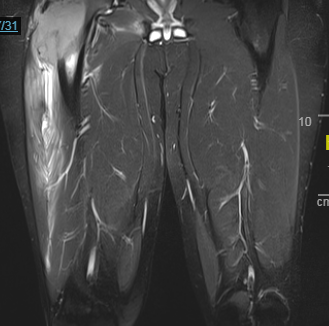

Case Presentation: A 20 year old male with past medical history significant for chronic phase CML, diagnosed approximately 1 year prior to admission, presents for evaluation of worsening right leg pain over the past 2-3 months. At the time of diagnosis of CML, he was started on Imatinib and shortly after developed diffuse bone pain. Repeat bone marrow biopsy at 7 months showed minor cytogenetic response on Imatinib and patient was switched to Desatinib, with improvement in bone pain. Repeat bone marrow biopsy at 3 months following initiation of Desatinib showed patient to have complete cytogenetic response. Approximately one month later, patient began to notice worsening pain in his lower back and right hip. A MRI of the lumbar spine showed bulging disks of L3-L5 which was thought to be the cause of the pain. After several months of physical therapy and epidural spine injections the patient’s lower back pain resolved but he continued to have progressive hip pain that became so severe that he was unable to ambulate. On admission, his right lower extremity was exquisitely tender on range of motion testing. MRI of right femur was obtained which showed proximal large mass with bony destruction and extra osseous extension into the adjacent musculature. Biopsy of mass was obtained which came back significant for femoral sarcomatous transformation of patients CML. Hospital stay was complicated by pathologic fracture of the right hip. Given the size and extent of the sarcoma no intervention was possible at the time. He was started on induction chemotherapy (CLA + pinotinib) in an attempt to shrink the mass and subsequently underwent 2 more rounds of consolidation chemotherapy with reduction in size of R femur mass. He is currently being followed as an outpatient by orthopedic surgery for possible surgical intervention and is also being evaluated by bone marrow transplant team for future haploidentical transplant, as his brother has been identified as suitable donor.